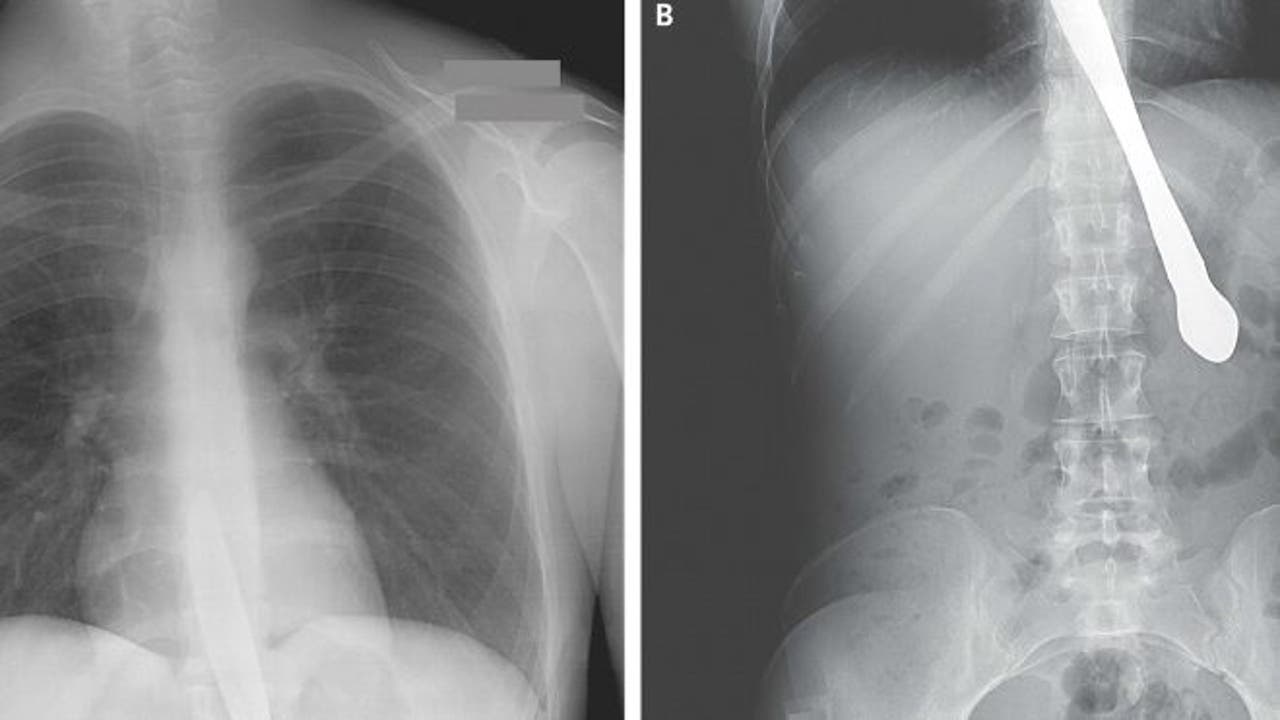

A 30-year old woman was taken to the emergency room after accidentally swallowing a butter knife, the New England Journal of Medicine (NEJM) reported.

But when she laughed, she accidentally swallowed the knife, lodging it in her esophagus, according to NEJM.

Doctors had to perform surgery to remove the knife, but said there was no additional damage to her esophagus or stomach. The woman was able to begin eating again without complications.